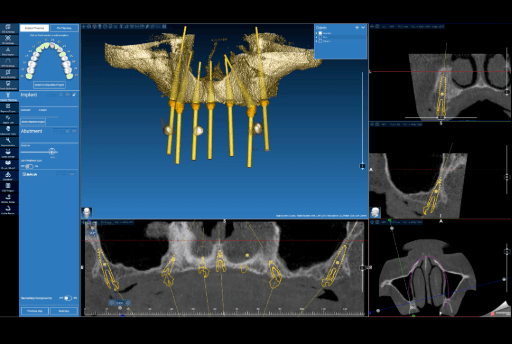

2.2 Implant Planning and Surgical Guide Design

Upon the CBCT with integrated data, the implant planning was performed using Real Guide. A total of seven implants were planned for the upper arch, including two pterygoid implants to ensure posterior anchorage. Six implants were planned for the lower arch. The implant distribution was planned to optimize anteroposterior spread and reduce cantilever length. Based on this virtual implant planning, a surgical guide with fixation pins was subsequently designed.

Implant planning (Real Guide) for the upper arch.

Implant planning (Real Guide) and fixation pins for the surgical guide for the upper arch.